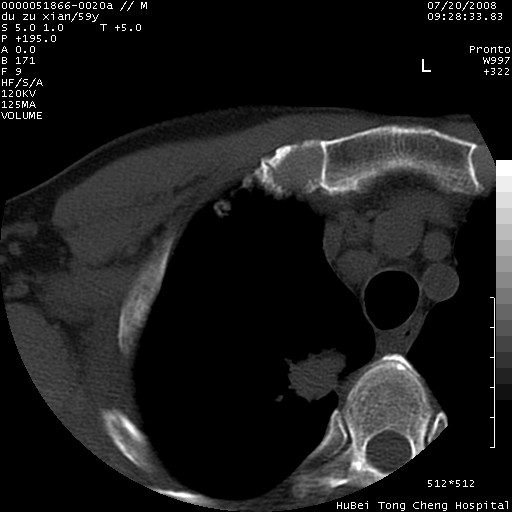

以下是引用宇宙ct在2008-8-25 23:21:00的发言:[br]右肺周围性肺癌并肋骨转移,纵隔淋巴结转移。

以下是引用zsl6918在2008-8-25 22:40:00的发言:[br]右肺周围性肺癌并肋骨转移,纵隔淋巴结转移。

以下是引用zy_zj在2008-8-26 15:24:00的发言:[br]单从病变本身,我倾向良性炎性病变,但肋骨转移了,所以说是考虑右肺周围性肺癌并肋骨、纵隔淋巴结转移可能性大。